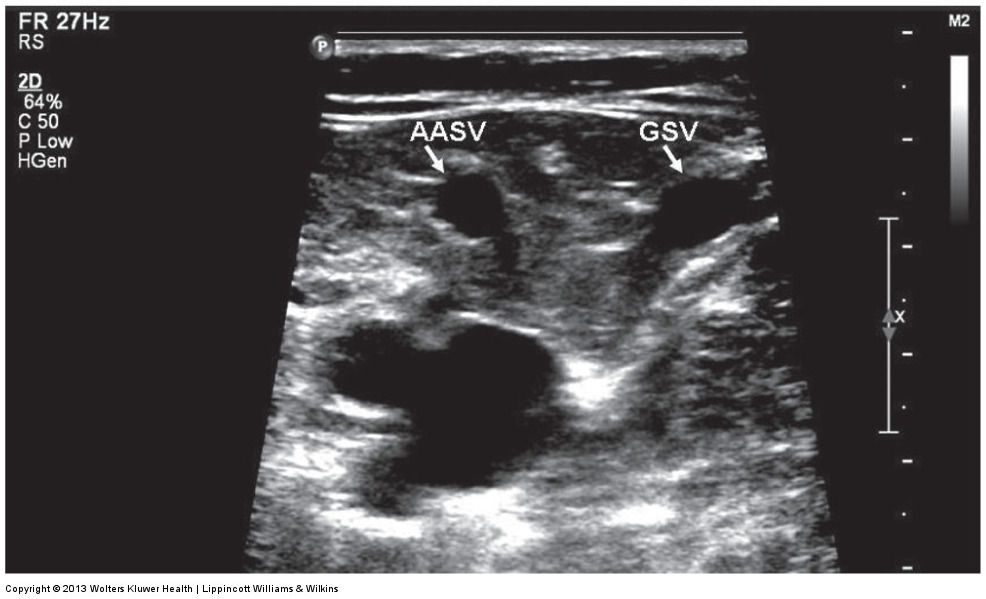

anterior accessory saphenous vein (AASV)

is aligned with femoral artery and vein in a transverse plane; lies within a saphenous compartment

ultrasound image of the alignment sign